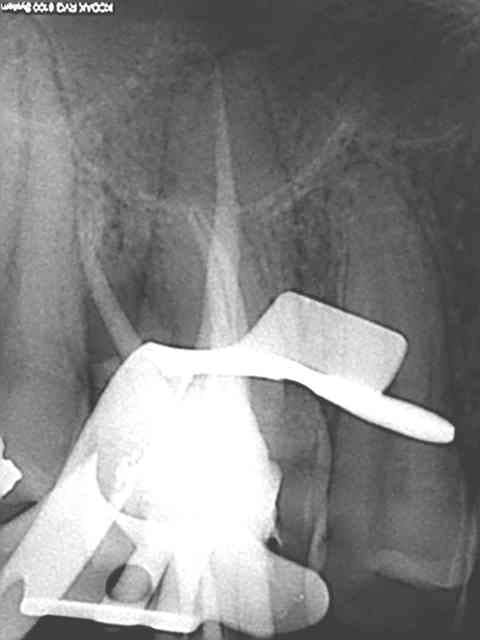

instruments utilisés : sx, s1,R25,Mtwo 25, largo 3, crown down (au 2 tiers dela racine environ voir plus) avec sx r25 largo, puis S1 sur protaper sur endo master jusqu'à l'apex, R25 à l'apex et Mtwo sur endomaster pour vérifier la lt en 25 . Ca marche à tous les coups.

L'instrument unique est un mythe sur les canaux difficiles par contre le r25 arrache à mort et ne casse jamais il remplace les S2,F1,F2 protaper.

Et une de plus !

C'est pas de la frime hein, mais ca fait plaisir d'avoir trouvé ENFIN une technique rapide et reproductible sans casse. (enfin presque il y a dans le tas un micro morceau de R25 pas loin de l'apex )